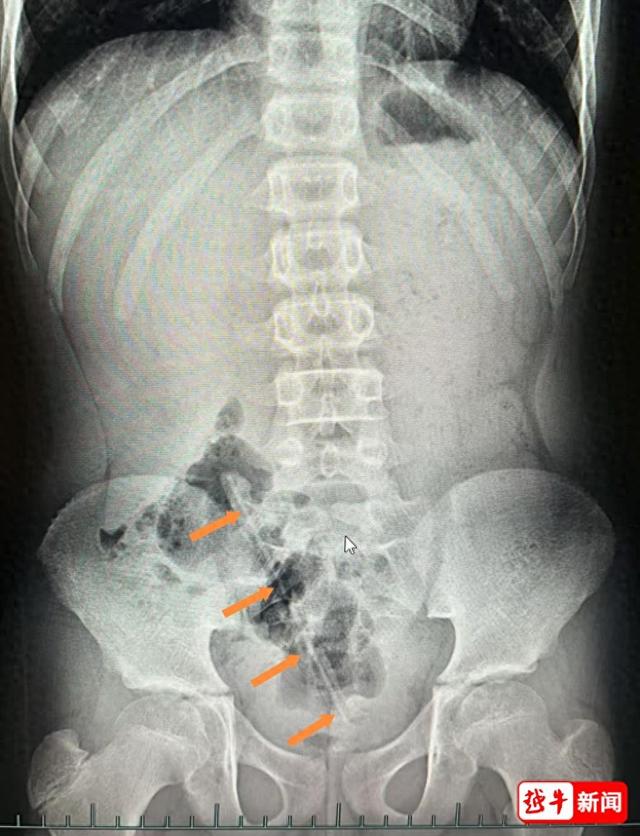

小兒外科醫生屠菊英查體時在患兒右側臍旁觸及一條狀物體,但肛門指檢卻未能探及異物。急診腹部X線檢查顯示:盆腔內確有一條狀異物,長度約17cm。

鑒於異物已滯留體內3天,存在直腸或結腸黏膜損傷甚至穿孔的風險,且滯留時間越長風險越大,該院小兒消化科副主任醫師劉偉榮趕至現場會診。經與小兒外科團隊討論后,決定立即為小木施行急診腸鏡檢查及腸鏡下異物取出術。

小木塞進肛門裡的鉛筆↓